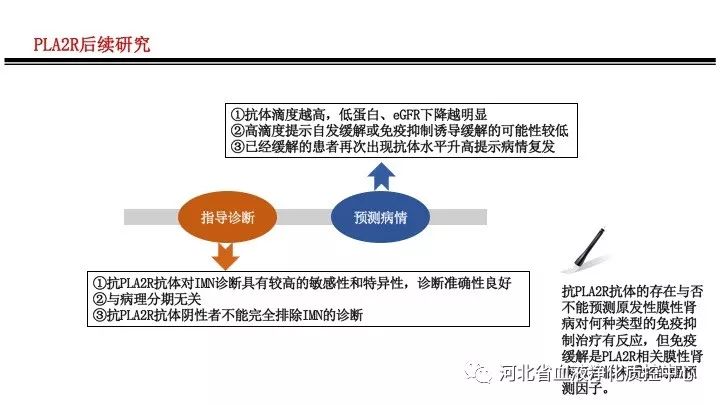

关于原发性膜性肾病PLA2RAb,不可不知的

关于原发性膜性肾病PLA2RAb,不可不知的